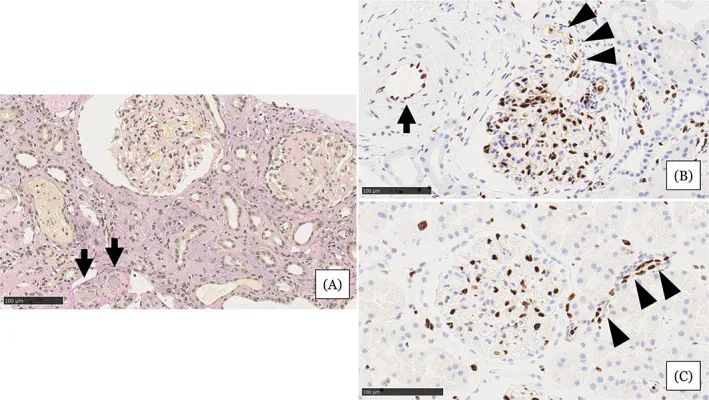

在住院第31天進(jìn)行的腎活檢結(jié)果

圖注:在住院第31天進(jìn)行的腎活檢結(jié)果。A,顯示小動(dòng)脈被粘液性內(nèi)膜增厚(箭頭)堵塞,腎小球萎縮,毛細(xì)血管壁起皺,嚴(yán)重的間質(zhì)單核細(xì)胞浸潤伴腎小管損傷。B,EC細(xì)胞核的缺乏在小動(dòng)脈(箭頭)中很突出。在相鄰的小動(dòng)脈(箭頭)中注意到不同大小的不規(guī)則細(xì)胞核。C,EC的等距核在血壓正常的腎臟供體的腎臟小動(dòng)脈中形成有序的線。比例尺 =100μm